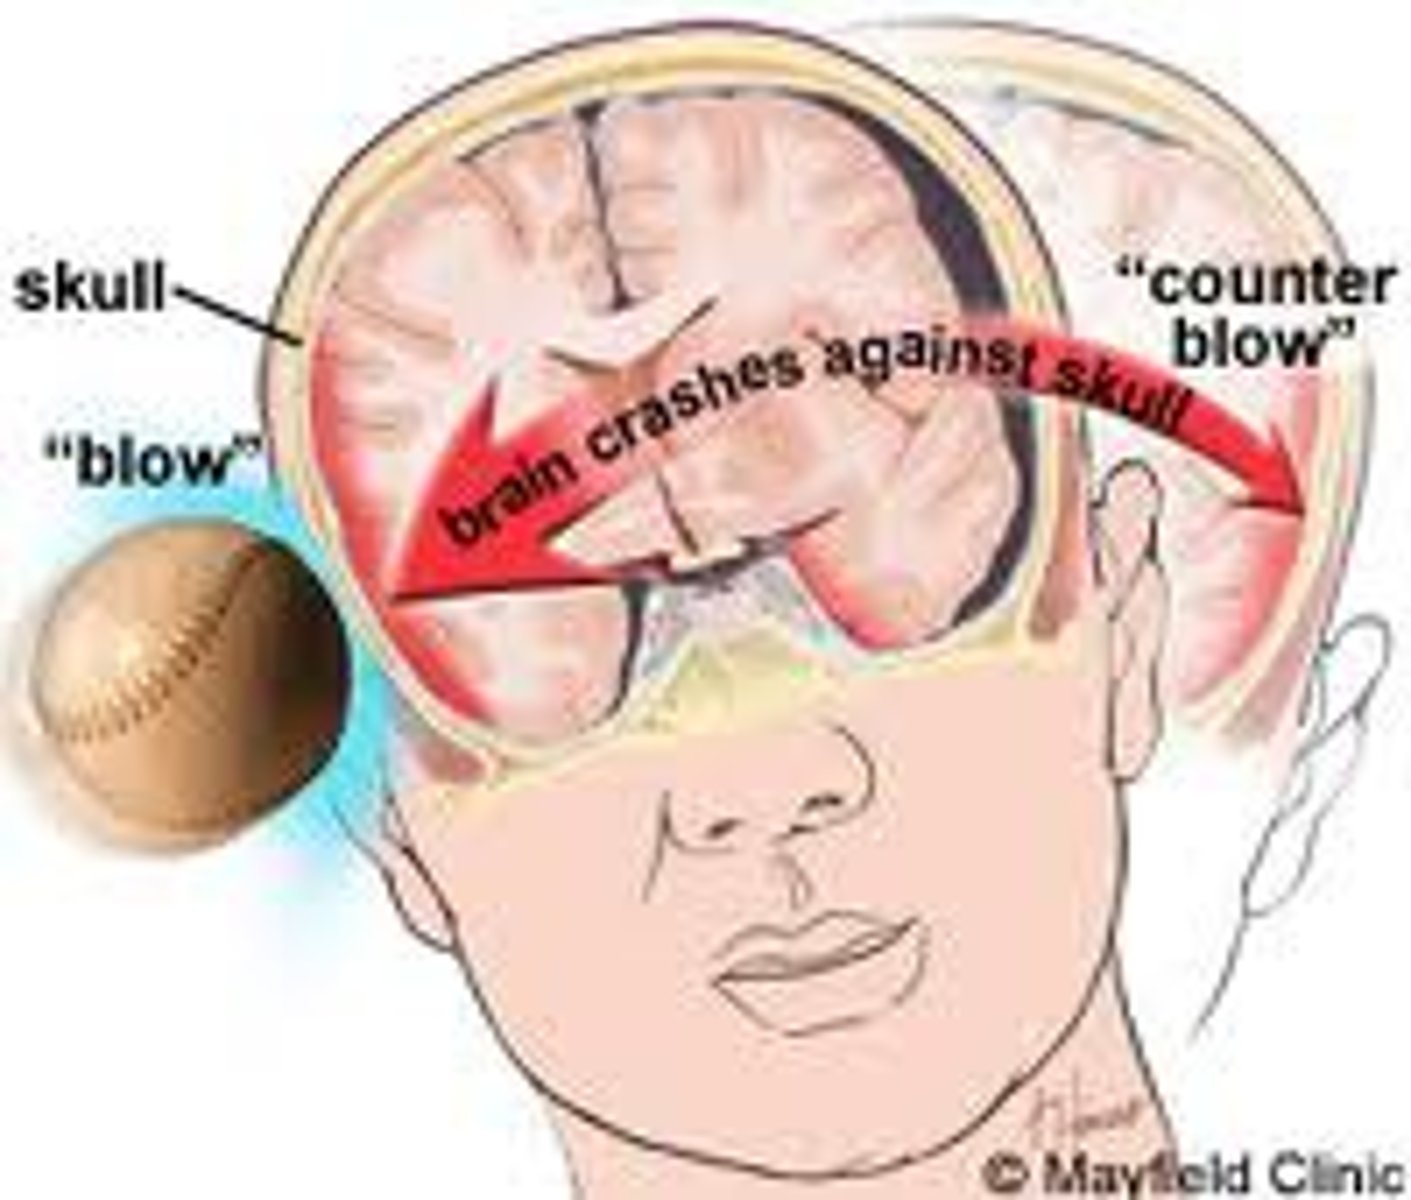

Traumatic brain injuries (head trauma)

1) a leading cause of accidental death in U.S.

2) Caused not only by localized injury at site of blow but also by ricocheting effect as brain hits opposite end of skull